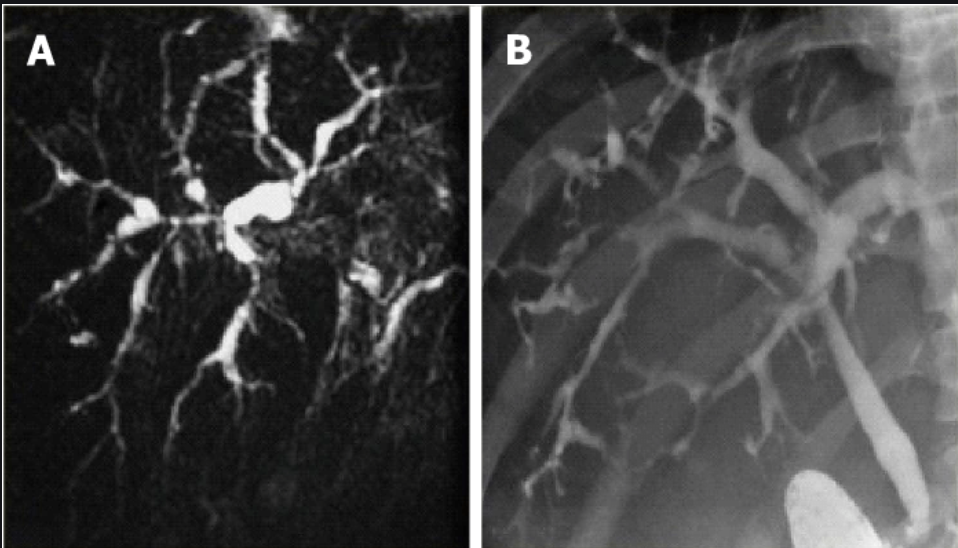

Bile duct infection/inflammation: PSC

ERCP/MRCP: app; which parts of the biliary tree most affected?